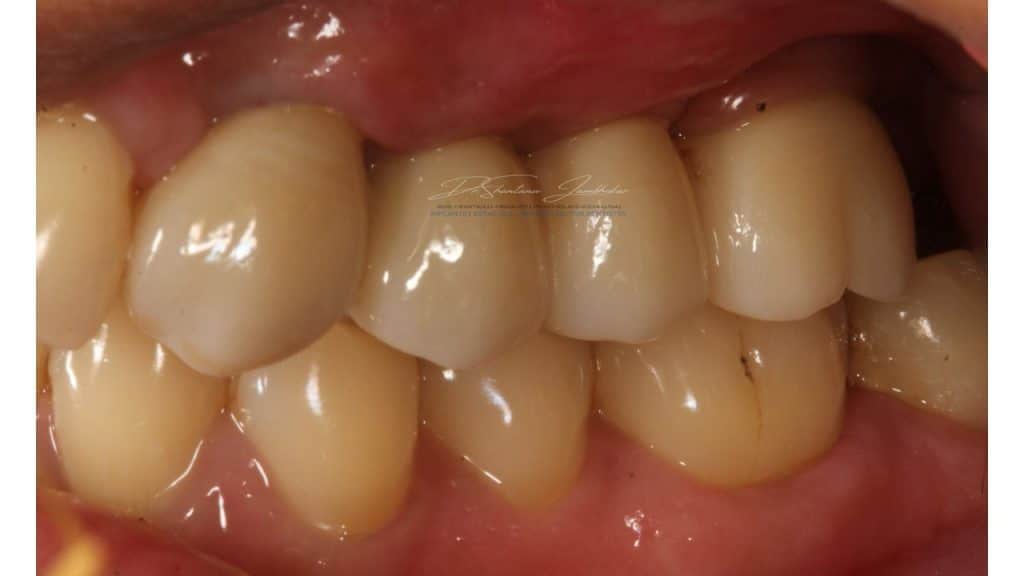

Cement retained Monolithic Zr Implant Restorations with 23 & Screw retained Monolithic Zr Implant restorations using Ti-base abutment with 24-25-26

Post treatment image at 12 months followup

Post Treatment Follow up at 22 months